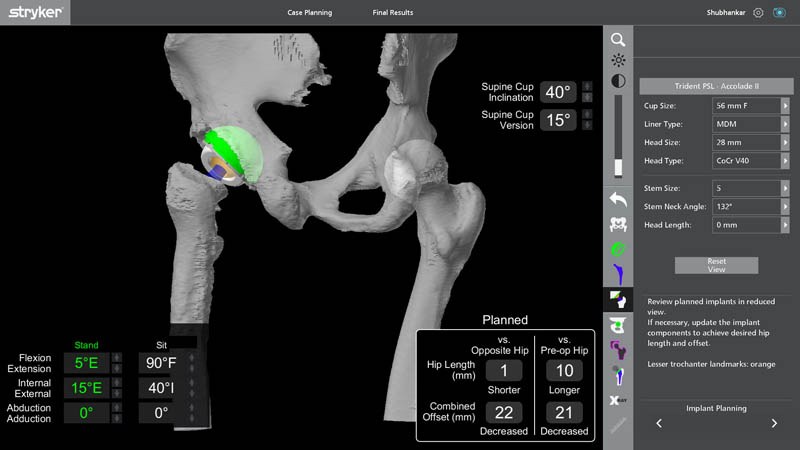

Preoperative Planning

- 3D Preoperative Planning with Segmentation

o Detailed separation (segmentation) of bone, old implant, and soft tissue - Accurate Assessment of Bone Loss

- Improved Stability & Longevity of the New Implant

- Reduced Risk of Repeat Failure

Segmentation is an advanced imaging and planning process where CT-based data is converted into highly detailed 3D anatomical models. This allows the surgeon to:

- Anticipate surgical challenges before entering the OT